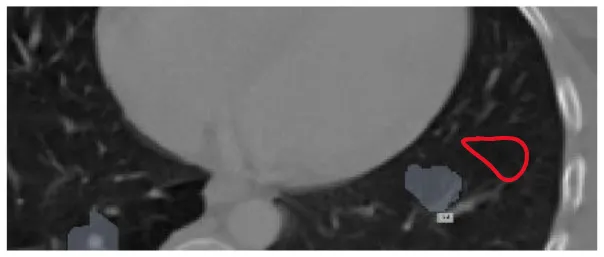

After preprocessing the image, shown in the Figure 11A the grouped picture, Figure 11B what was found when Lung tumors were identified. Figure 11C results of cutting lung tumors into whole pieces. Figure 11D the findings of the lung tumor search. Figure 11E picture showing the effects on a specific area of lung tumors when they are cut into pieces. Figure 11F a picture of a lung tumor that was accurately cut into pieces.

Figure 11

Utilizing the provided approach, we performed visual segmentation of heterogeneous lung nodules. (A) Clustered image. (B) Segmented image. (C) Extracted image. (D) Extracted image with nodules localizations. (E) Nodule capture. (F) Nodule region highlighted.